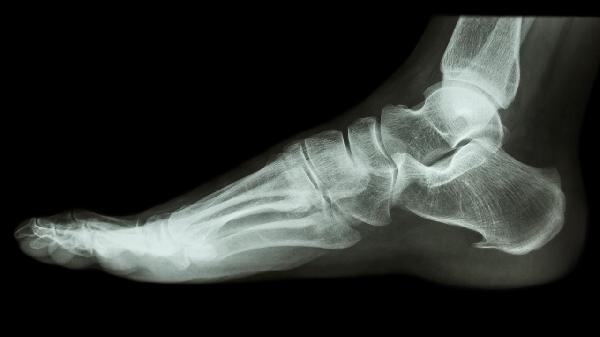

脚后跟骨裂多长时间能恢复 脚后跟骨裂的四个恢复方法分享

脚后跟骨裂的恢复周期可分为三个阶段。1-2周为急性期,需严格制动避免负重,此时疼痛肿胀明显,建议使用拐杖辅助行走。3-6周为愈合期,可在医生指导下逐步进行非负重活动,通过X光监测骨痂形成情况。6-12周为功能恢复期,多数患者可逐步恢复轻度负重,但完全承重需经专业评估。恢复期间需避免跳跃、奔跑等剧烈运动,防止二次损伤。定期复查对判断愈合进度至关重要,延迟愈合者可能需要延长固定时间。

卧床制动是骨裂初期的基础治疗,需保持患肢抬高15-30度以减轻肿胀。支具固定多选用行走靴或石膏托,需持续佩戴4-8周,每日检查皮肤受压情况。物理治疗包括超声波和低频脉冲电磁场,能促进局部血液循环,每周进行2-3次。药物镇痛可选用布洛芬缓释胶囊或对乙酰氨基酚片,但须避免长期使用。营养补充应注重钙质和维生素D摄入,每日建议饮用300-500毫升牛奶,适量进食鱼类和坚果。康复训练应从被动关节活动开始,逐步过渡到抗阻练习,整个过程需在康复师指导下进行。